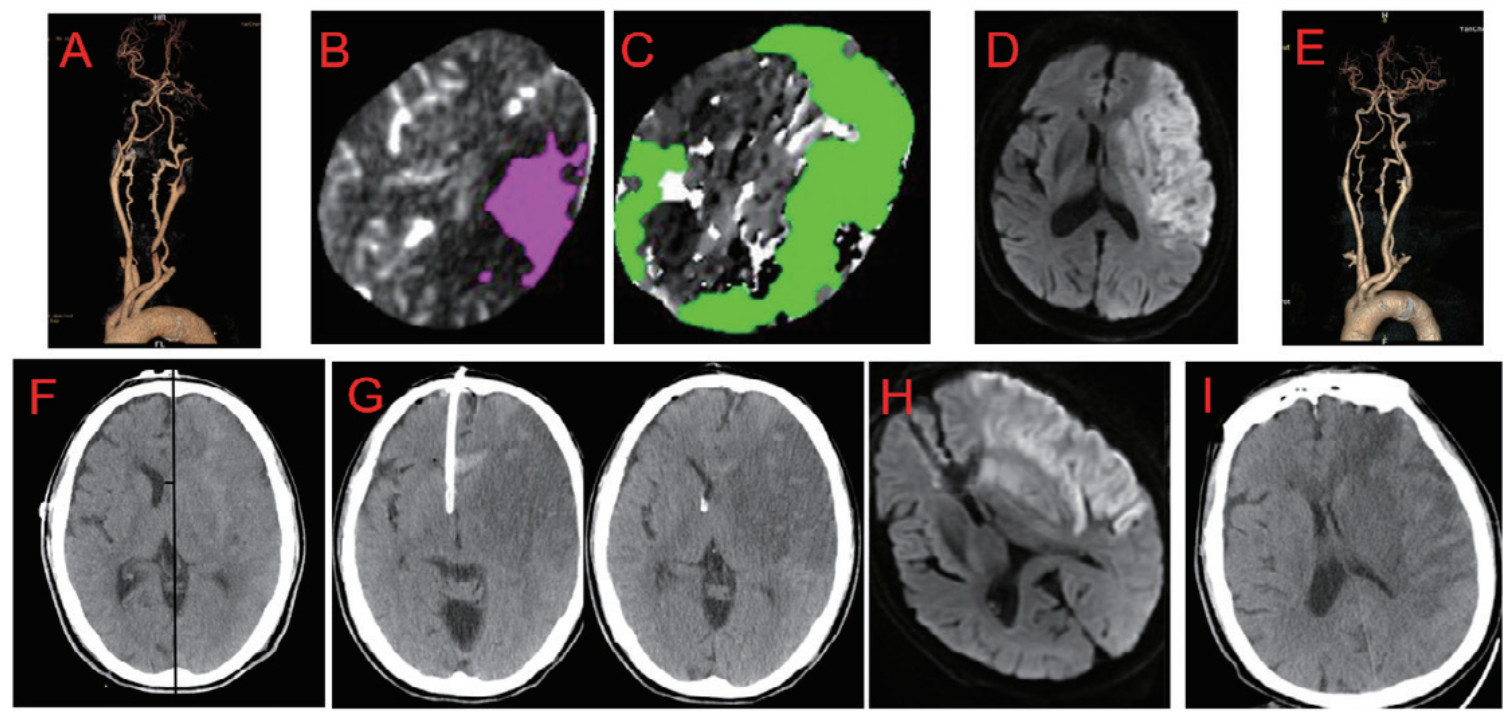

案例2 大面积脑梗死取栓术后伴恶性脑水肿患者,男,75岁,因“被发现意识不清3 h余”入院。取栓术后恶性脑水肿形成,给予梗死对侧脑室置管颅内压监测+外引流。术后11d,中线复位,脑室复张,转康复科康复(图 4)。

|

| 注:男,75y。既往高血压病史,被发现意识不清3 h余。急诊头颈CTA示左侧颈内动脉闭塞(见图4A);脑灌注示:CBF < 30% volume:63 mL(见图4B);Tmax > 6.0 s volume:605 mL(见图4C)。行取栓手术治疗,成功再通,术后当天MRI提示大面积脑梗死,梗死区超过大脑中动脉供血区的2/3(见图4D),取栓后复查CTA示闭塞血管再通(见图4E)。取栓后第2 d, 患者持续昏迷,复查CT示同侧脑室压闭,中线移位7 mm,提示恶性脑水肿形成,术前测量最佳内偏角0º或稍偏内(见图4F),给予梗死对侧脑室置管颅内压监测+外引流(见图4G)。术后4 d复查MRI示占位效应未加重(见图4H)。术后11 d,中线复位,脑室复张(图4I),转康复科康复 图 4 大面积脑梗死取栓术后伴恶性脑水肿患者 Fig 4 A patient with LHI accompanied by malignant brain edema after thrombectomy |